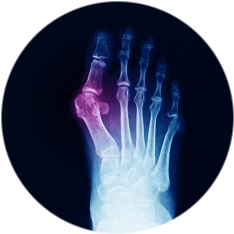

Вальгусная деформация 1 пальца стопы отличается не только развитием болевых ощущений, но и наличием видимых эстетических недостатков. Показания к оперативному лечению определяет грамотный специалист, на основании жалоб. Помимо этого, он обращает внимание на материалы проведенных обследований, уточняет анамнестические сведения. Операция проходит планово по четкому алгоритму, поэтому не занимает много времени и лишена негативных последствий. С целью обезболивания во время хирургического вмешательства используется местная или общая анестезия.

- появление «косточки» в области первого пальца стопы (вальгусная деформация средней и тяжелой степени);

- Рентген стопы

- УЗИ стопы

- КТ стопы